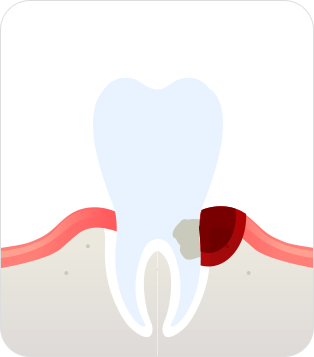

치주염(중기 ~말기)

치석이 점점 뿌리 쪽으로 내려가

염증이 깊어져 치조골 손실